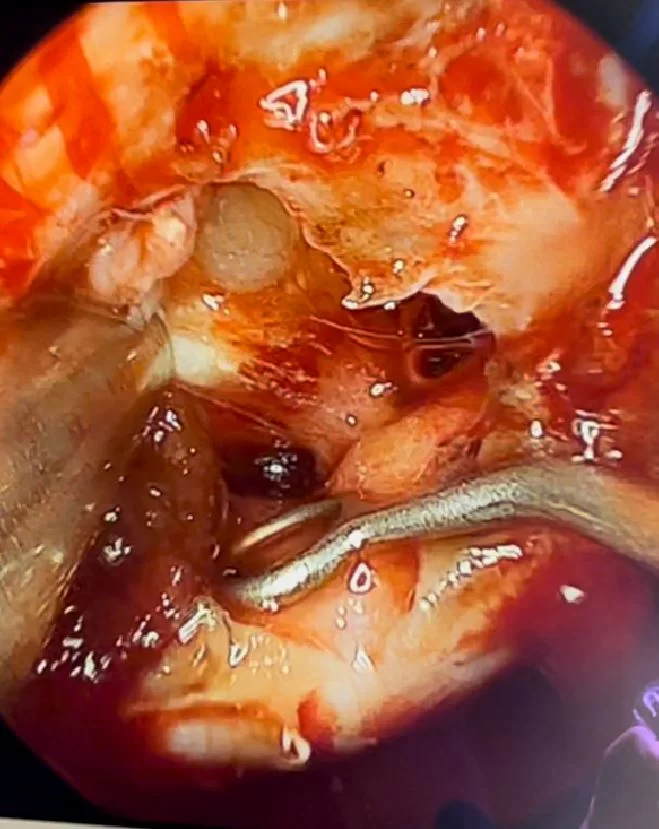

Αποφασίστηκε και διενεργήθηκε διαρρινική (δηλαδή μέσα από τη μύτη) ενδοσκοπική αφαίρεση του όγκου. Η αφαίρεση ήταν ολική.

Τα κρανιοφαρυγγιώματα είναι καλοήθεις όγκοι οι οποίοι μπορούν να αναπτυχθούν τόσο σε παιδιά όσο και σε ενήλικες. Συνήθως “κολλάνε” ισχυρά με τους πέριξ ιστούς και πιέζουν τα οπτικά νεύρα. Συχνά, η ολική αφαίρεση είναι δύσκολη και απαιτεί κρανιοτομία, δηλ. προσέγγιση του όγκου μέσα από τομή στο κρανίο.

Στη συγκεκριμένη ασθενή επιλέξαμε να αφαιρέσουμε τη βλάβη με τη βοήθεια του ενδοσκοπίου, μέσα από τη μύτη. Η ενδοσκοπική αφαίρεση επιτρέπει να ελεγχθεί πλήρως ολόκληρη η περιοχή του εφιππίου και να επιτευχθεί τελικά ολική αφαίρεση του όγκου χωρίς τομή στο κρανίο!